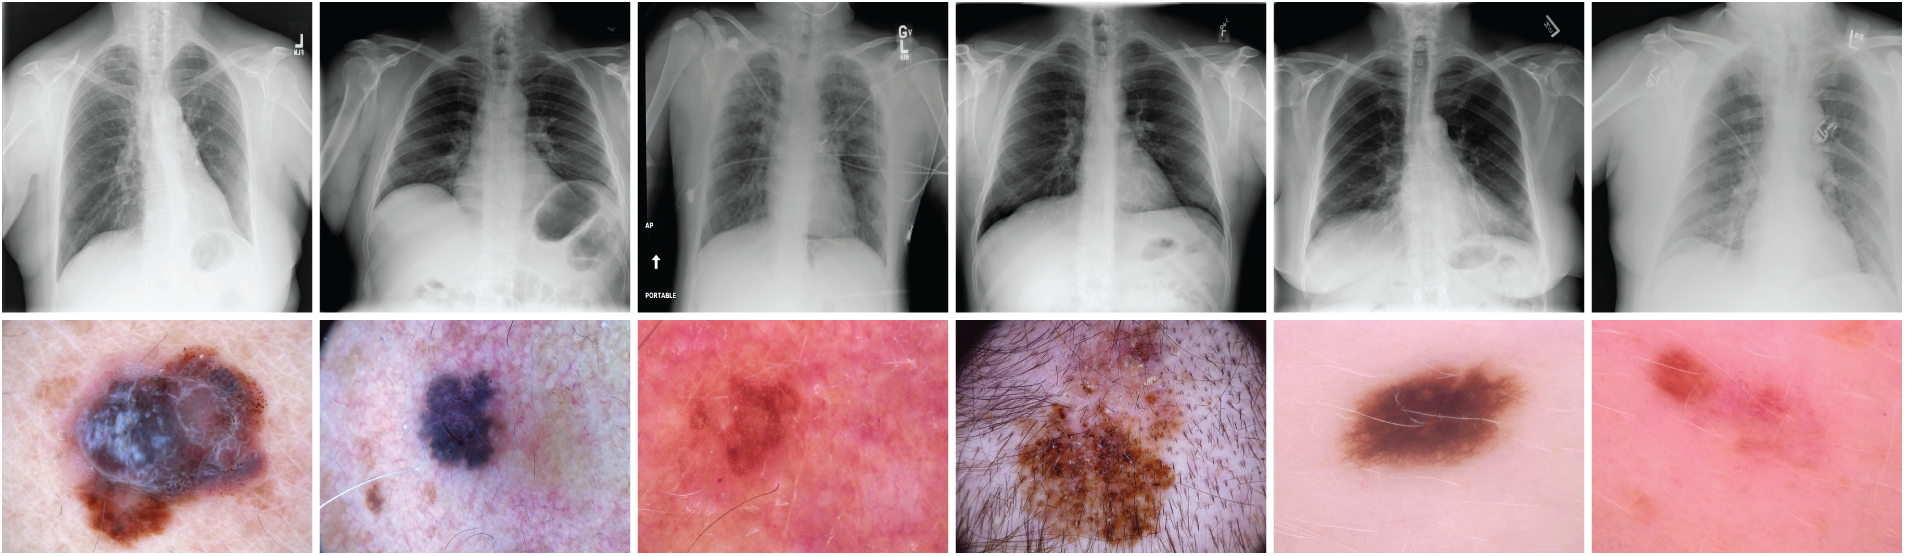

A fundamental challenge in medical image retrieval lies in managing the complexity and diversity of medical datasets, which often involve multi-label classifications [11]. Datasets such as ISIC-2018 [12,13] and ChestX-ray14 [1] pose unique difficulties due to the wide range of disease categories and the need for models to generalize across varying conditions. Fig. 1 presents sample images from these datasets, highlighting their complexity and diversity. Traditional CNN-based approaches often struggle to effectively capture both global and local features, particularly in multi-label classification settings [11,14].

Figure 1: Sample images from the ISIC-2018 [12] and ChestX-ray14 [1] datasets. These examples illustrate the diversity of medical conditions, including skin lesions (melanoma, basal cell carcinoma) and thoracic pathologies (pneumonia, cardiomegaly), emphasizing the need for robust models capable of accurate image classification and retrieval

We conducted experiments using two widely recognized medical imaging datasets: ISIC-2018 [12,13] and ChestX-ray14 [1]. Fig. 1 presents sample images from both datasets, illustrating the diversity and complexity of skin lesions and chest pathologies.